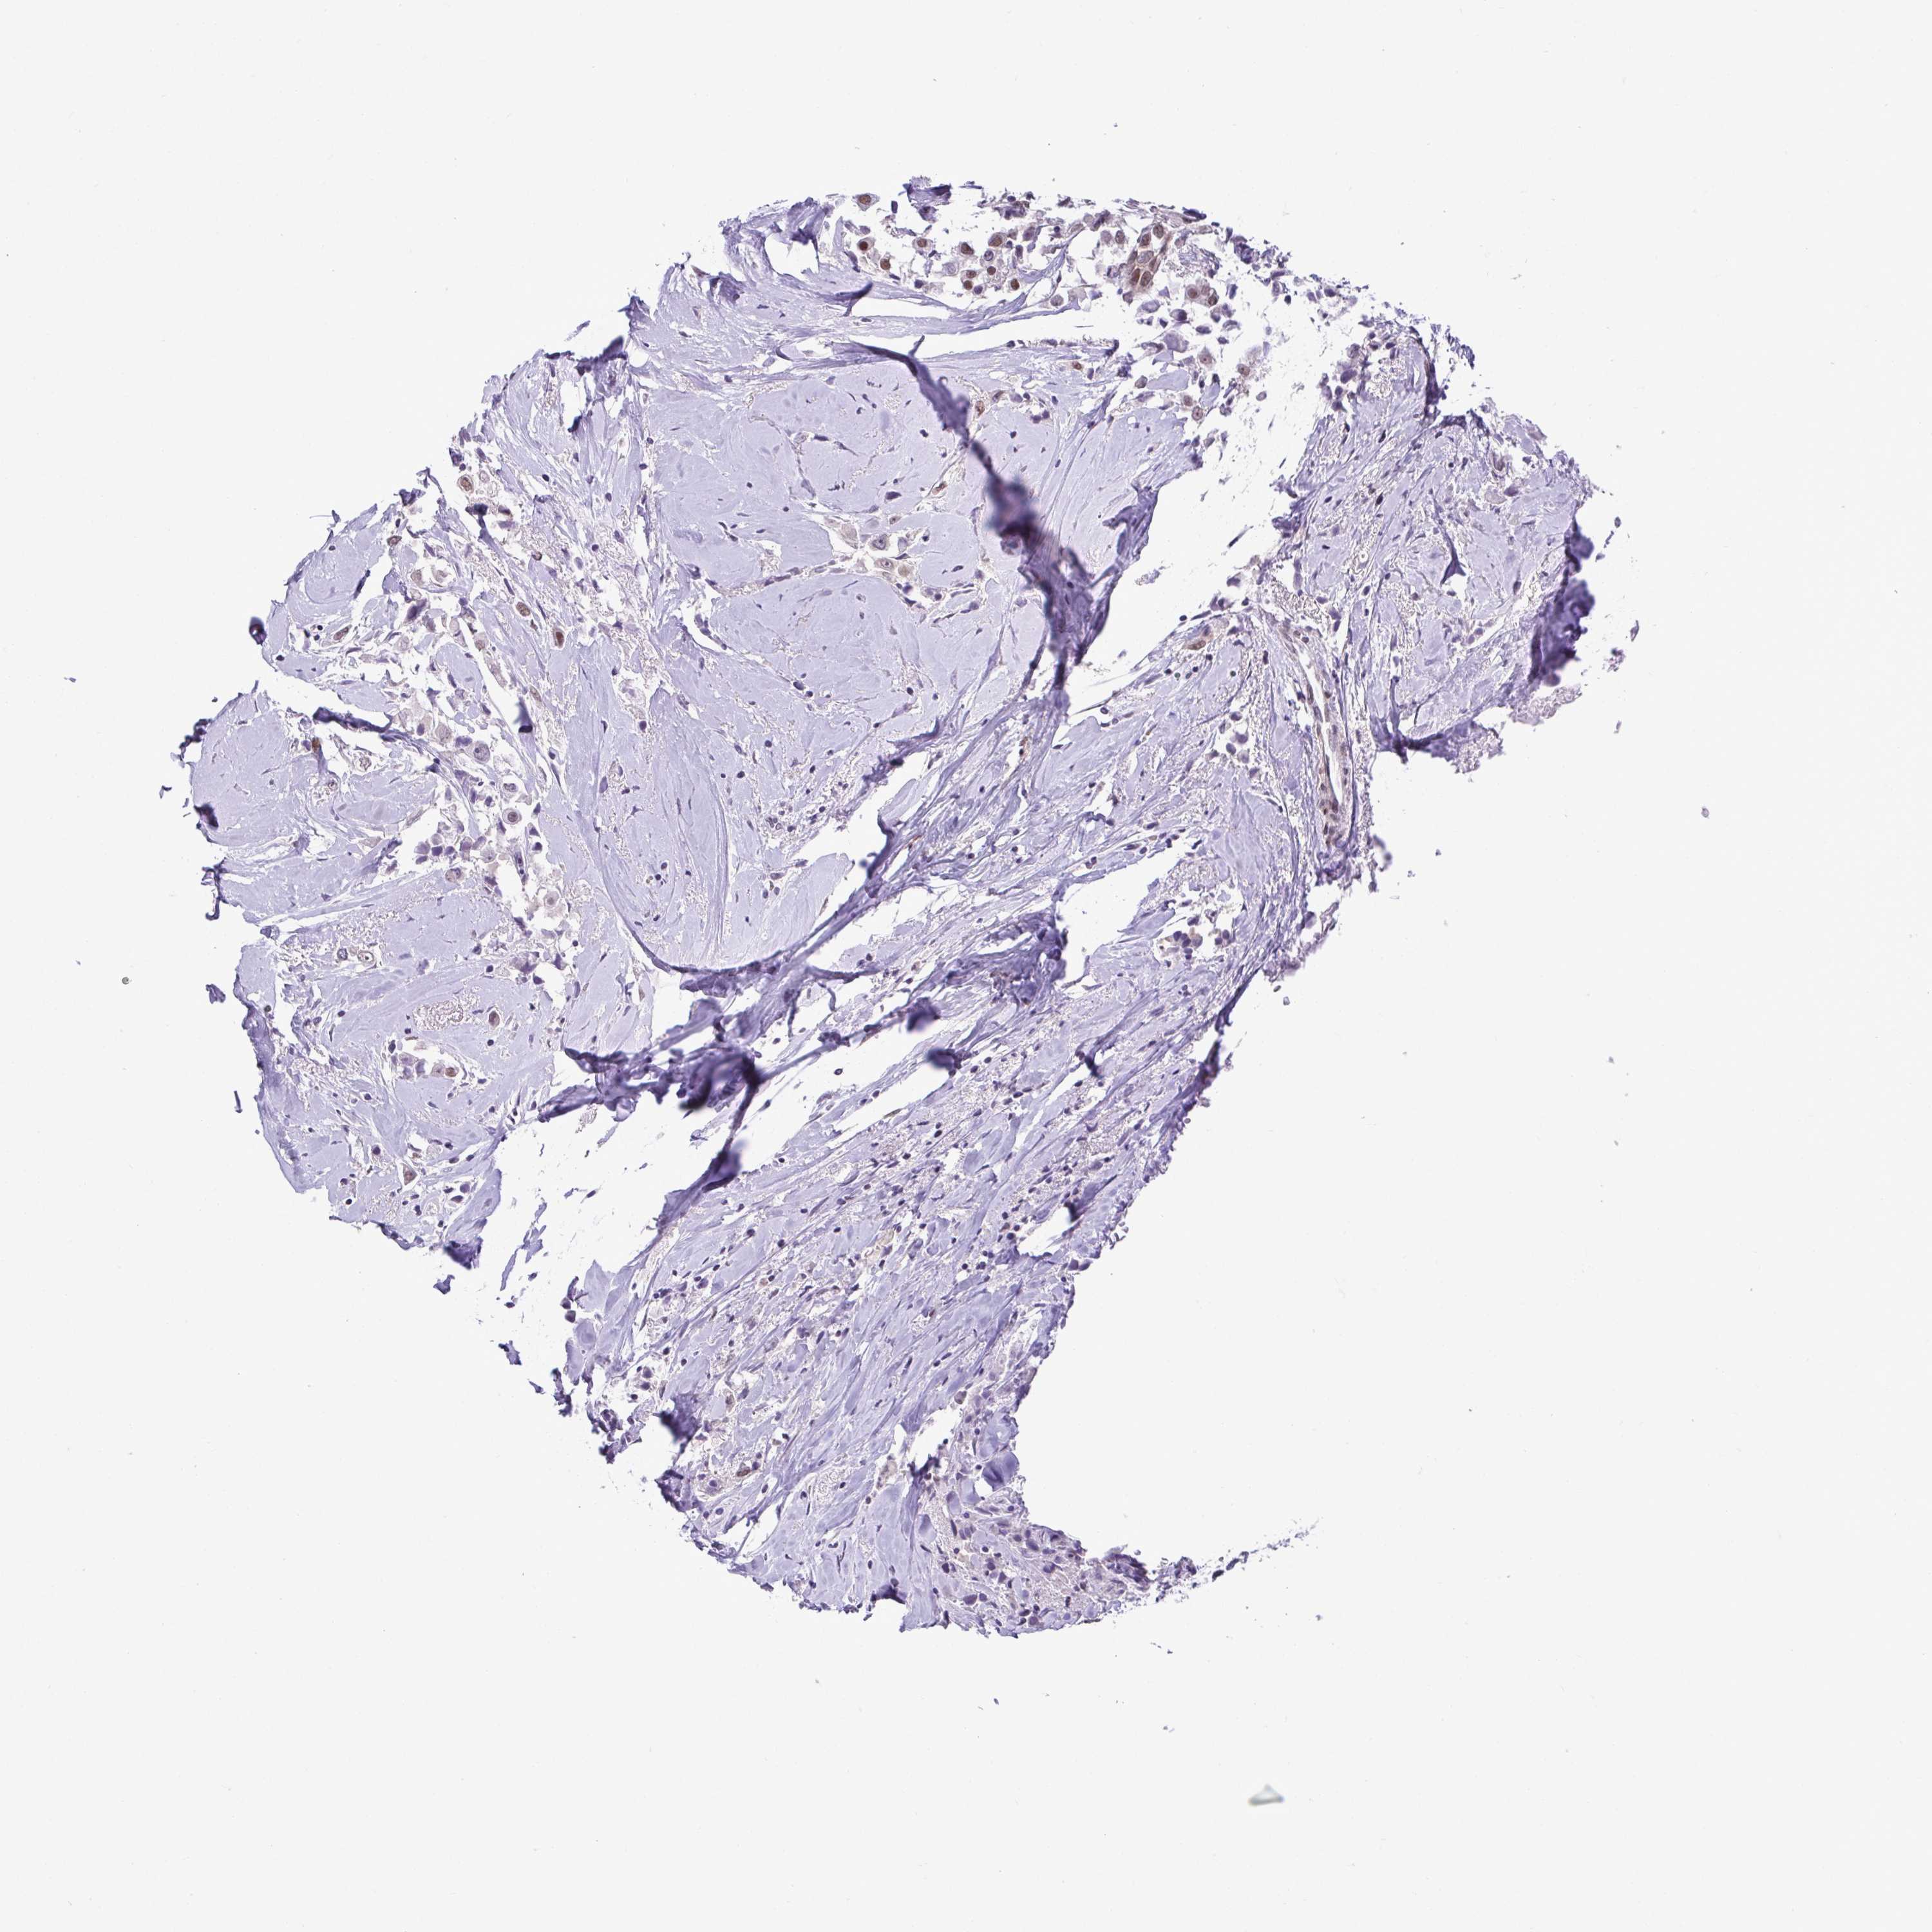

CANCER BREAST CANCER Show tissue menu

Breast cancer

Human cancer

Breast invasive carcinoma